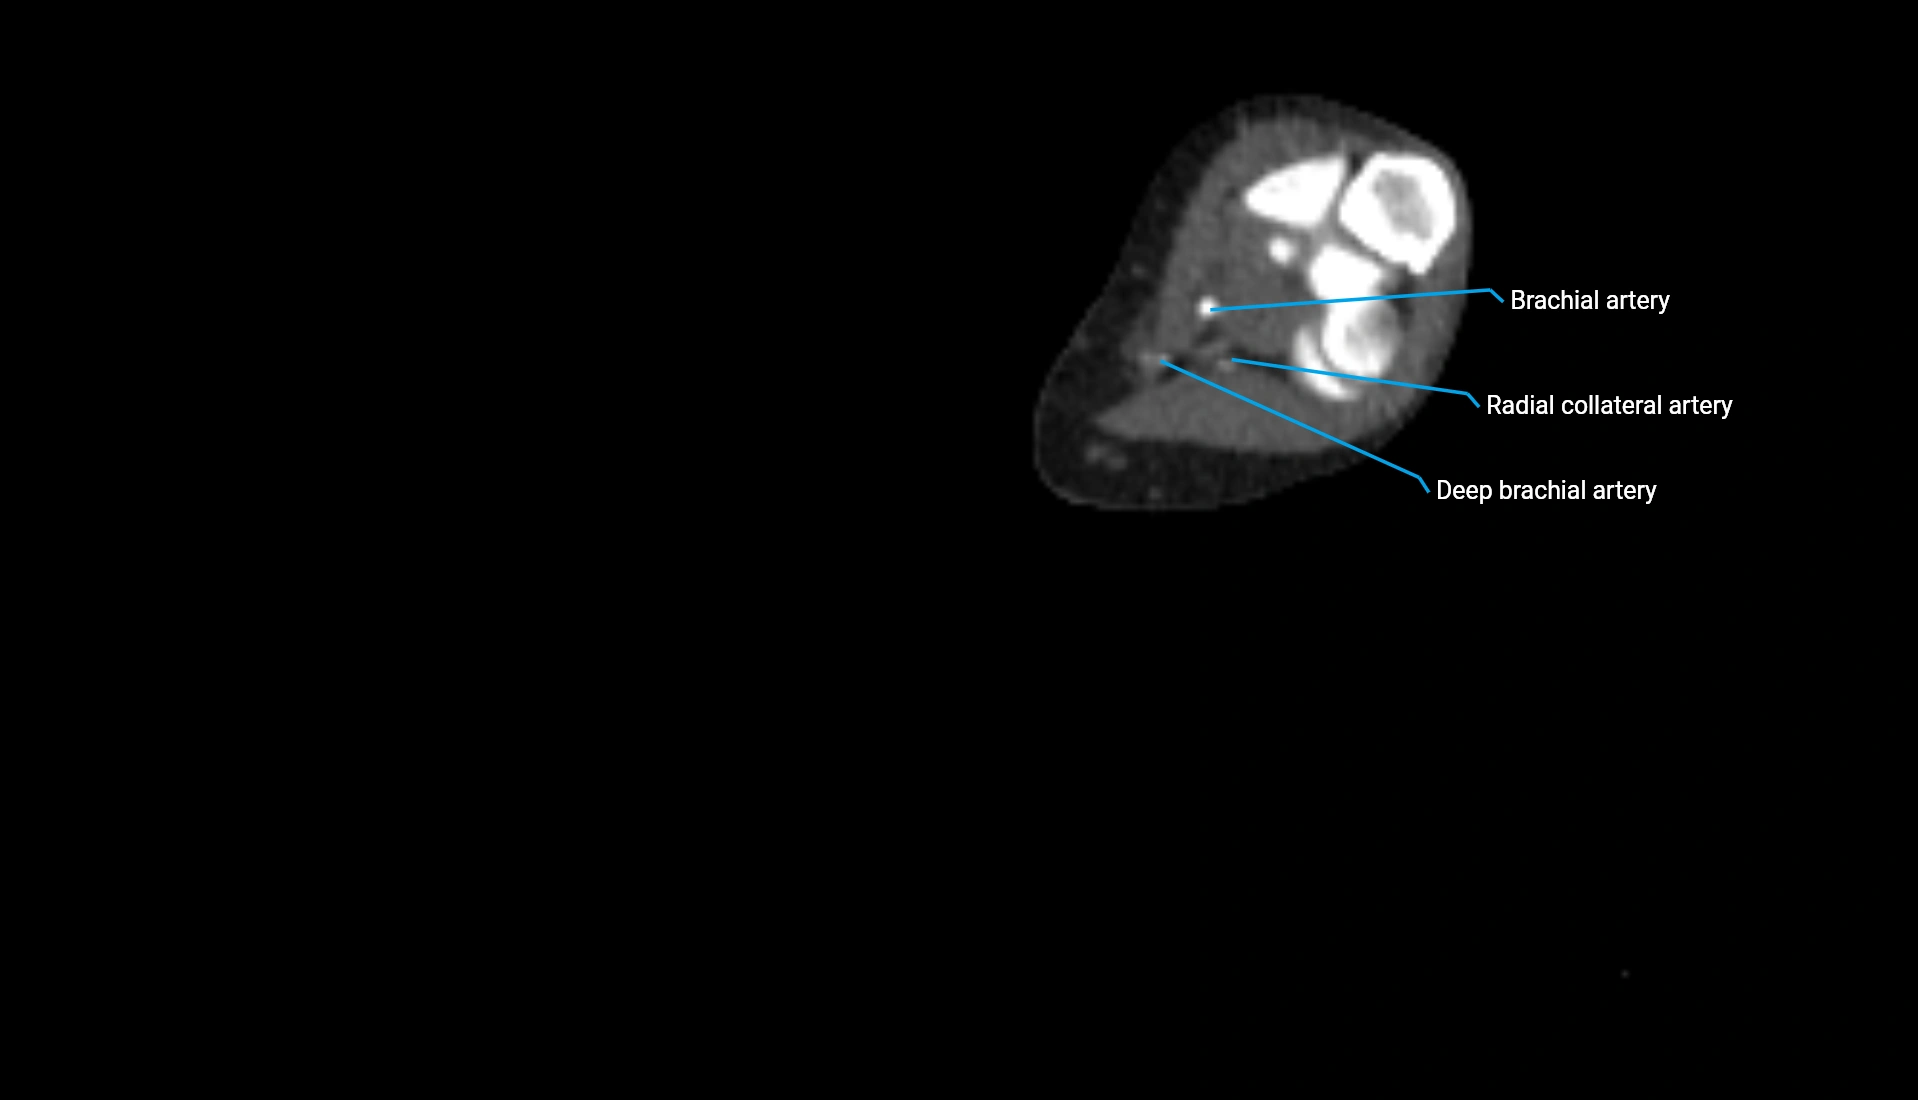

CT Appearance

Non-Contrast CT:

• Cortex: High-density, sharply defined

• Subchondral bone: Dense cancellous matrix

• Articular surface: Smooth concave contour articulating with the capitellum

• Excellent for evaluating bone integrity, alignment, and subtle fractures

Post-Contrast CT:

• Bone: No enhancement

• Joint capsule and synovium: Mild enhancement outlining the joint

• Improves contrast between soft tissues and bony margins

• Useful in detecting subtle joint abnormalities or postoperative changes